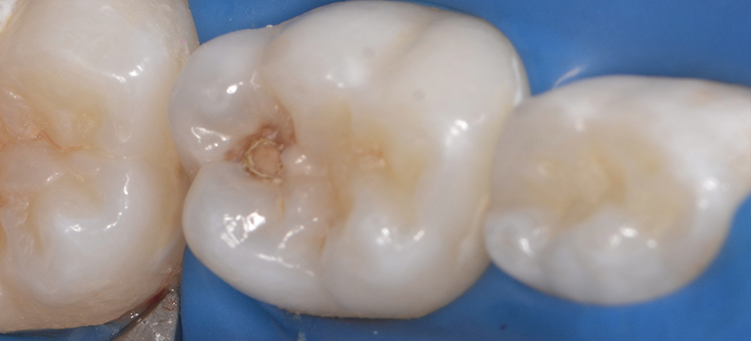

Лечение кариеса